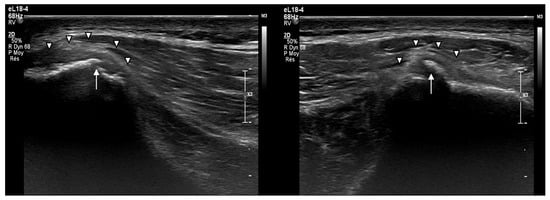

2.2. Imaging Findings

- Subperiosteal hematoma at the posterior iliac crest;

- A 20–25 mm detachment of the gluteus maximus;

- Partial involvement of the gluteus medius.

- Persistent cortical irregularities, including calcifications and periosteal thickening, on long-term follow-up.